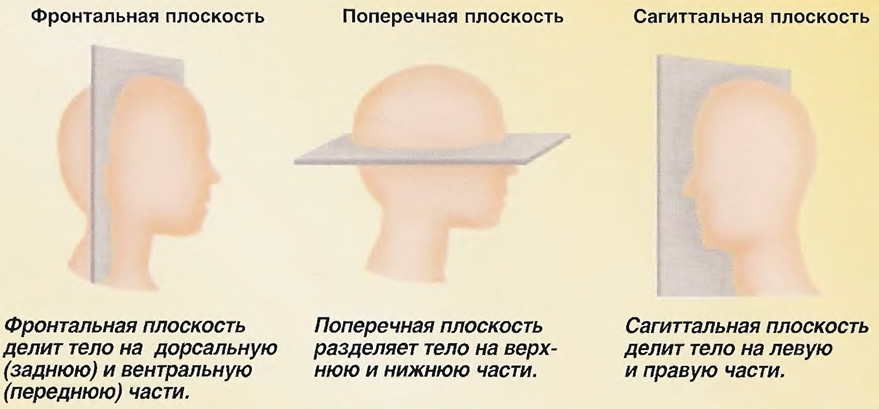

Анатомические изображения срединной сагиттальной линии черепа